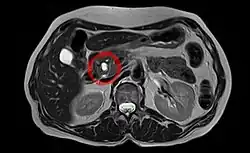

Intraductal papillary mucinous neoplasm in magnetic resonance imaging.